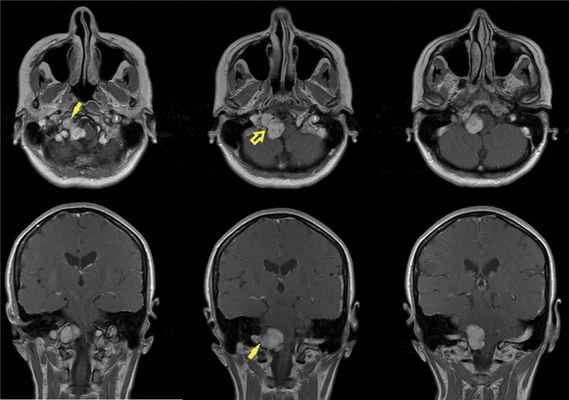

По данным МРТ головного мозга с усилением сигнала парамагнетиком выявлена опухоль парастволовой локализации справа, компримирующая продолговатый мозг и исходящая из расширенного канала подъязычного нерва. Меньший по размерам компонент опухоли располагался в полости канала и распространялся экстракраниально (рис. 1). Рис. 1. МРТ головного мозга пациентки В. до операции. При усилении сигнала выявляется опухоль справа, соответствующая невриноме, в форме «гантели», располагающаяся одной частью на уровне краниовертебрального перехода и вызывающая компрессию ствола мозга, а другой — частью в костных структурах.

При проведении МРТ головного мозга пациентки В. на 3-и сутки после операции выявлена остаточная часть опухоли в канале подъязычного нерва (рис. 5). Рис. 5. МРТ головного мозга пациентки В. на 3-и сутки после операции. При усилении сигнала парамагнетиком определяется остаток опухоли в канале подъязычного нерва справа (указано стрелкой).